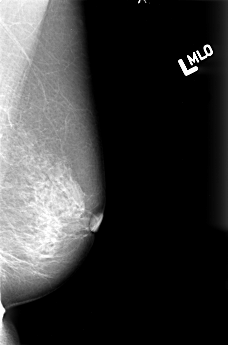

B_3016_1.LEFT_MLO

LEFT_MLO LINES 4480 PIXELS_PER_LINE 2952 BITS_PER_PIXEL 12 RESOLUTION 50 NON_OVERLAY